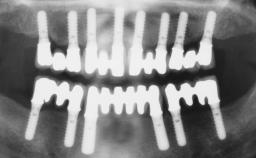

Rehabilitating an Edentulous Maxilla with a Fixed Dental Prosthesis Following Provisional Immediate Loading

This case features the flapless computer-guided placement of 7 bone-level implants, distributed to provide maximal support for the prosthetic framework. A rigid one-piece metallic framework was utilized as an interim restoration to reduce the risk of fracture associated with this prosthetic design. As part of the clinical examination, the SAC Assessment Tool was used, resulting in a surgical and restorative risk classification as “complex”.

# of Implants 7

Type of Implants Two-Piece

Guided Surgery Yes